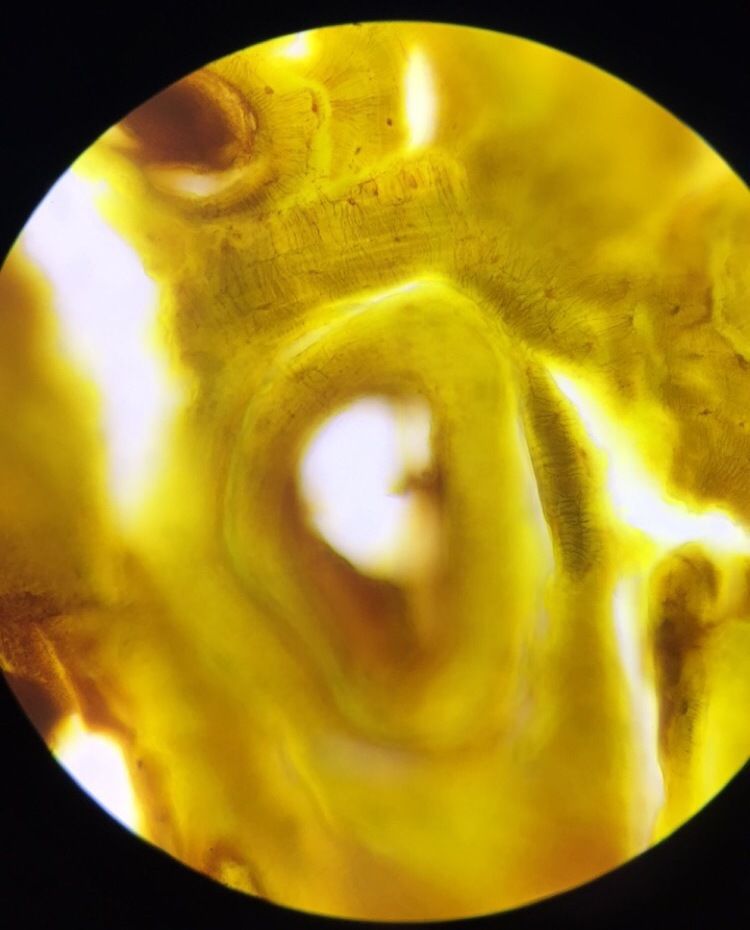

Image:

Simple Squamous (image/jpeg)

simple sqaumous impregnantion of silver nitrate |